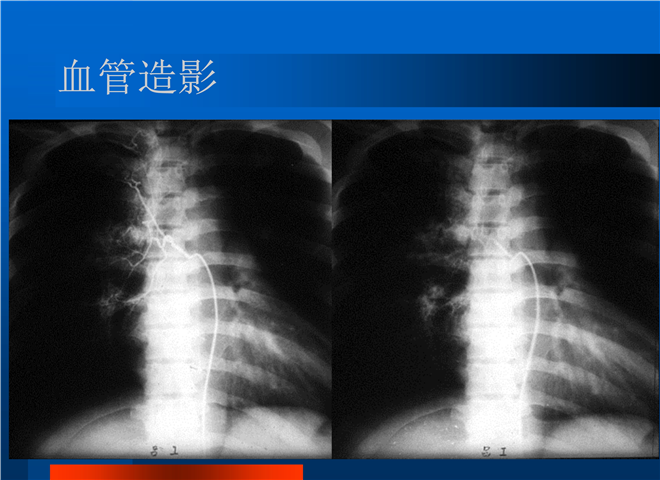

04_肺癌的介入治疗